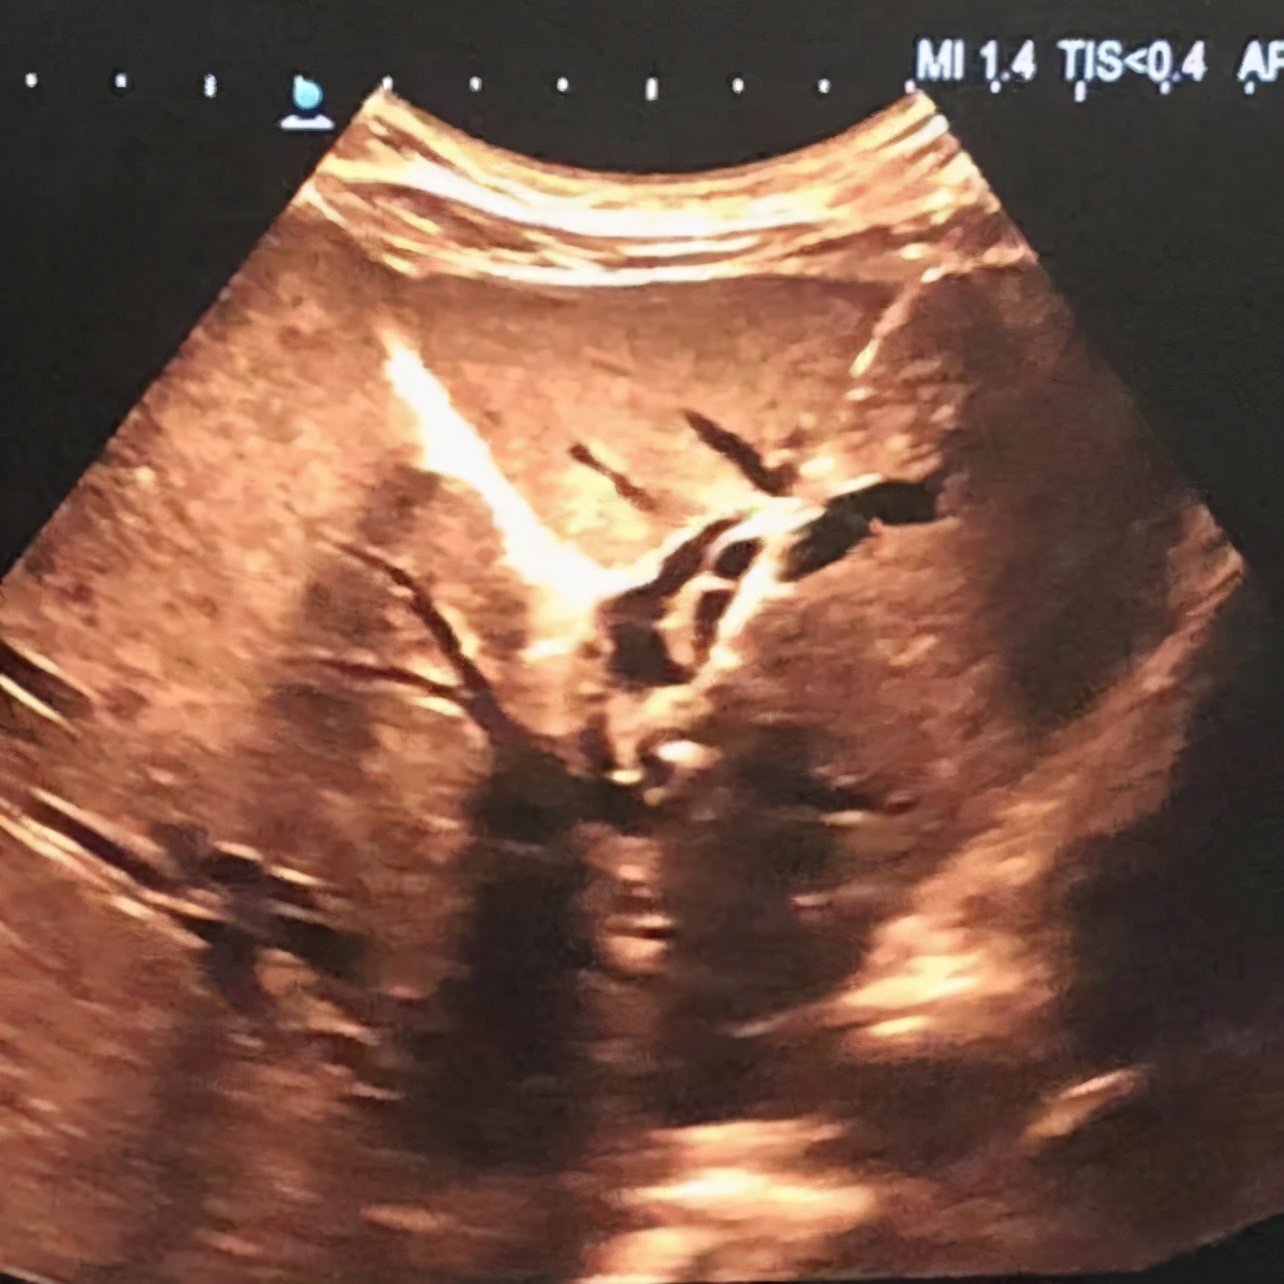

术中,医院超声科医师先为患者行超声检查,明确进针部位及进针方向,然后行局部浸润麻醉,在超声引导下将“邦特”引流导管管针穿刺进入患者扩张肝左叶肝内胆管内,抽出针芯,见墨绿色液体流出,拔出硬质套管,固定留置导管持续引流。手术仅10分钟即顺利完成。

术后进行超声复查,肝周未见明显积液回声。目前,患者胆红素已逐步恢复正常值,黄疸症状明显改善,已无腹痛、腹胀、恶心、呕吐情况,将择期进行“腹腔镜下胰十二指肠根治术”。